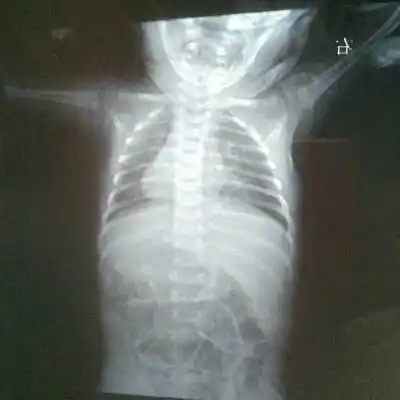

新生儿肺纹理粗不一定是肺炎,有可能是:新生儿湿肺

新生儿30天得肺炎,现在在妇幼icu,这是胸片,很严重吗

读片小儿胸片